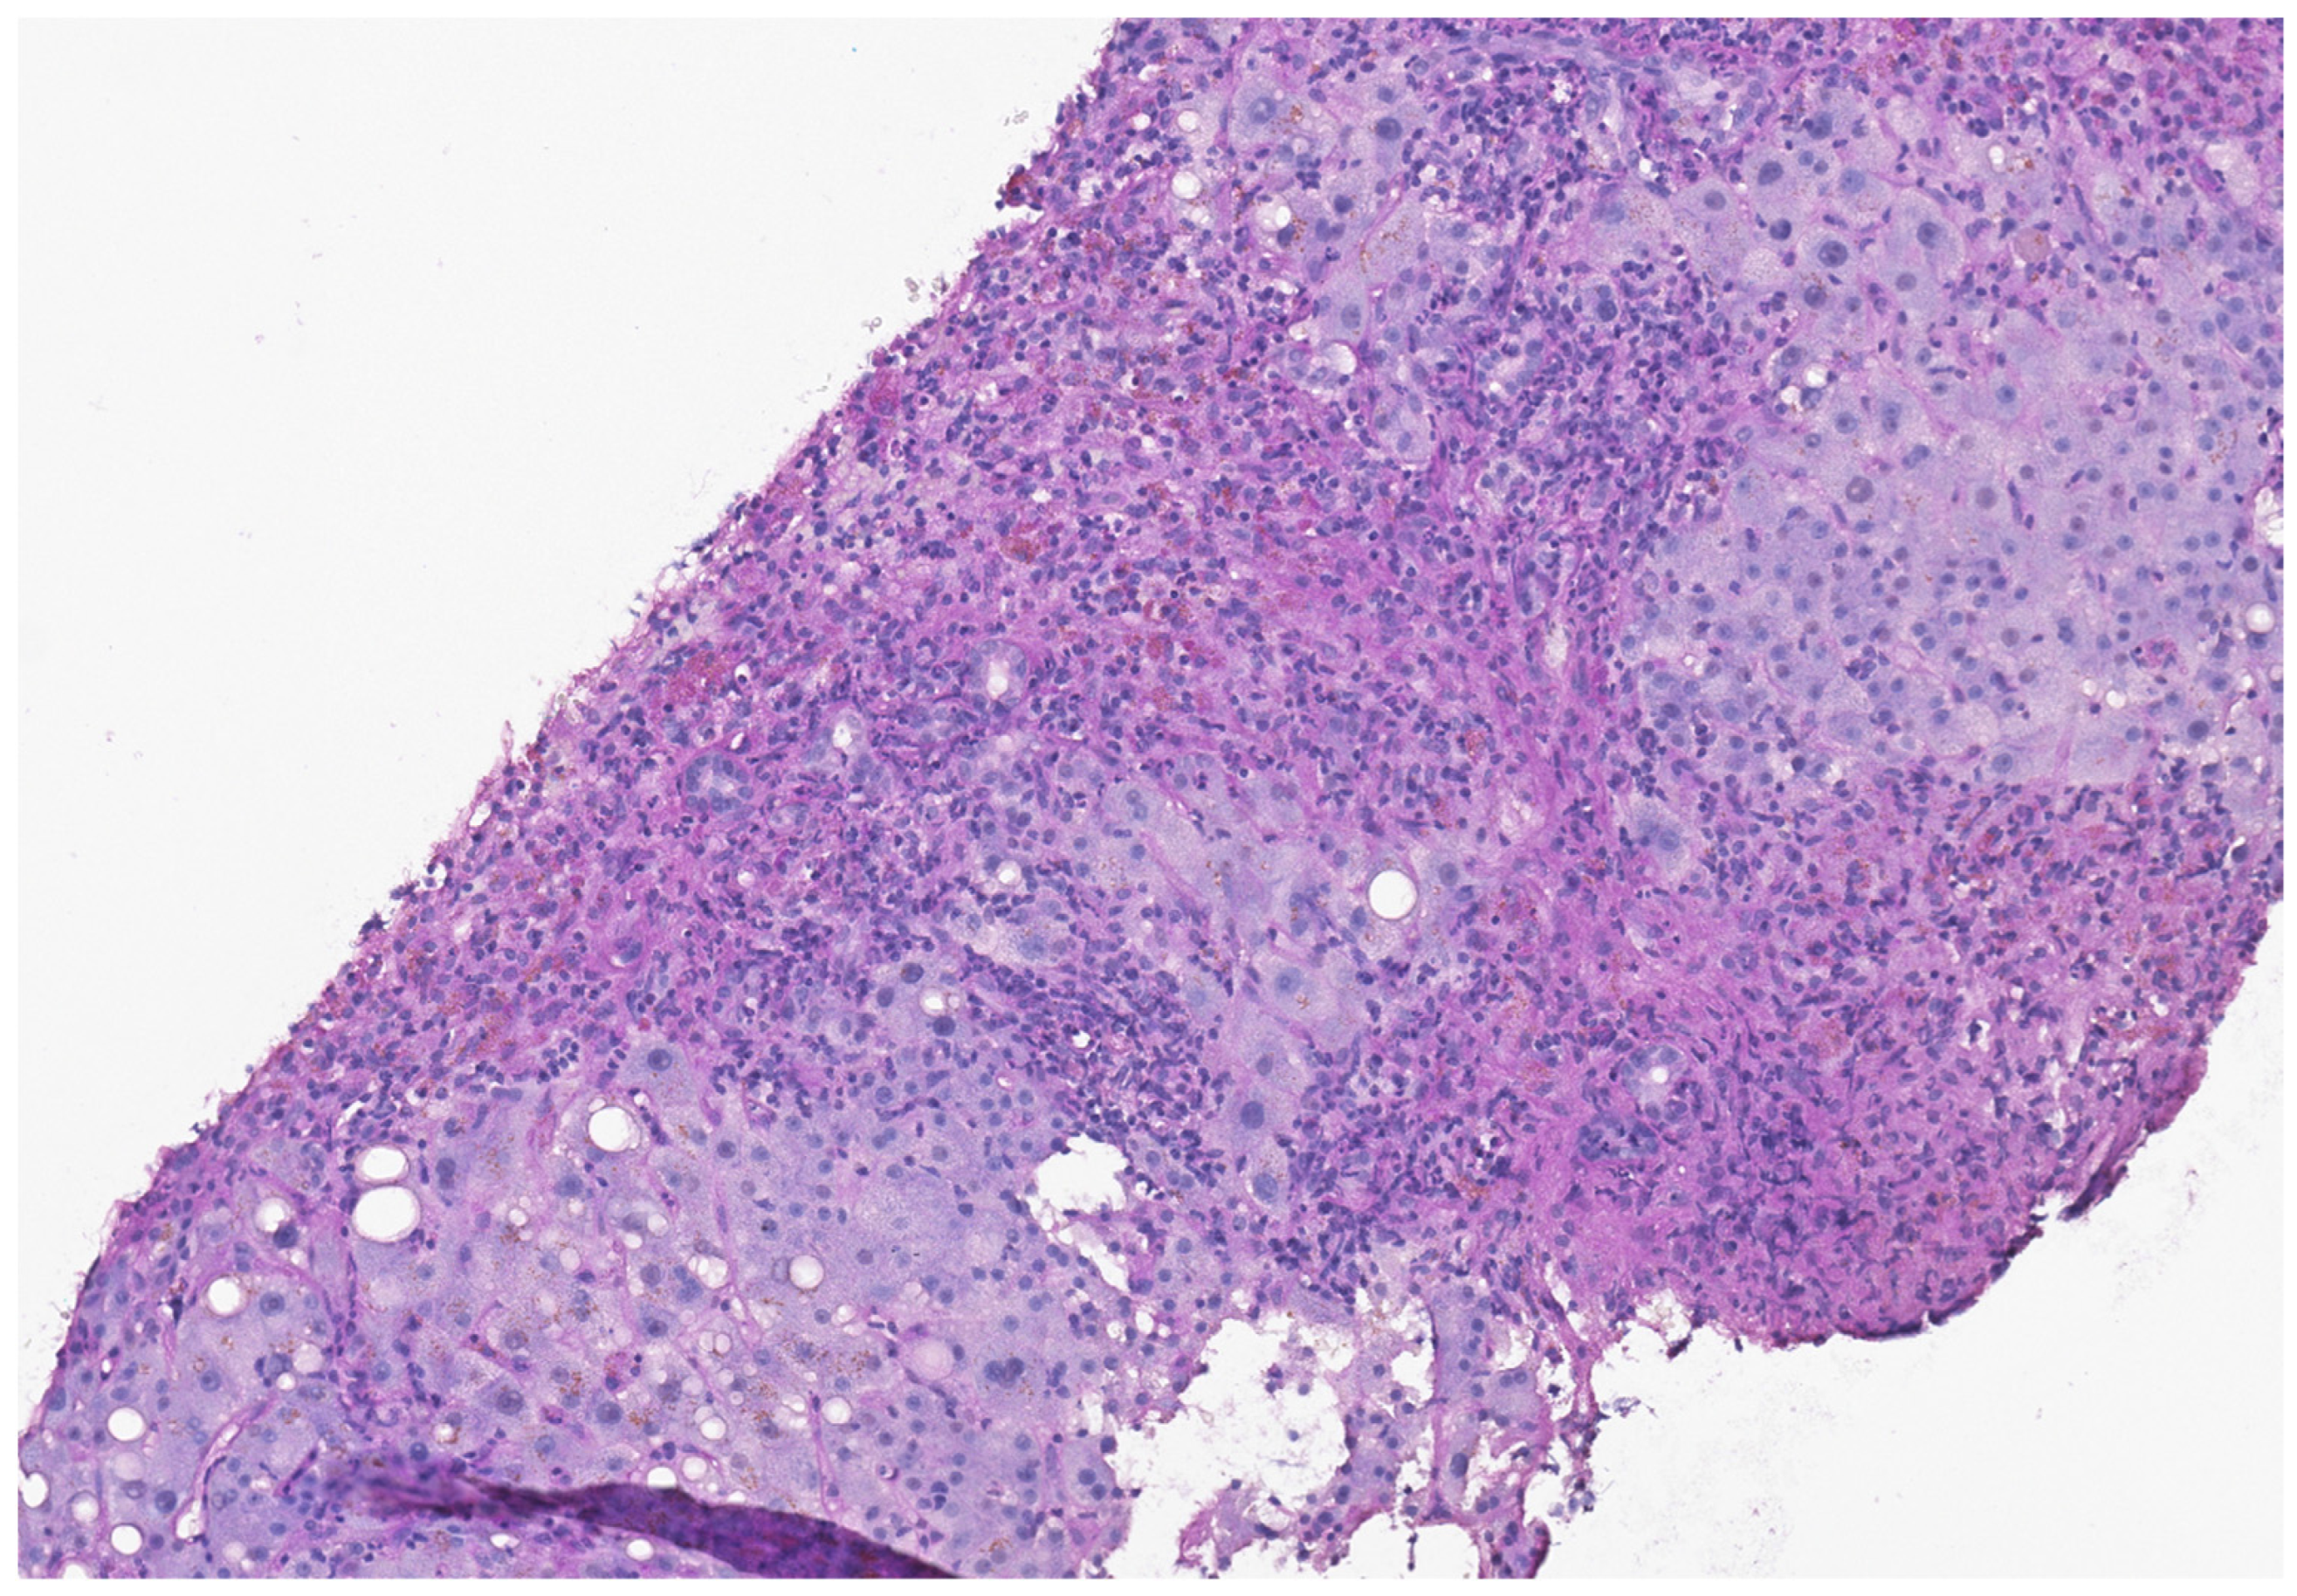

- Zen, Y.; Yeh, M.M. Hepatotoxicity of Immune Checkpoint Inhibitors: A Histology Study of Seven Cases in Comparison with Autoimmune Hepatitis and Idiosyncratic Drug-Induced Liver Injury. Mod. Pathol. 2018, 31, 965–973. [Google Scholar] [CrossRef] [PubMed]